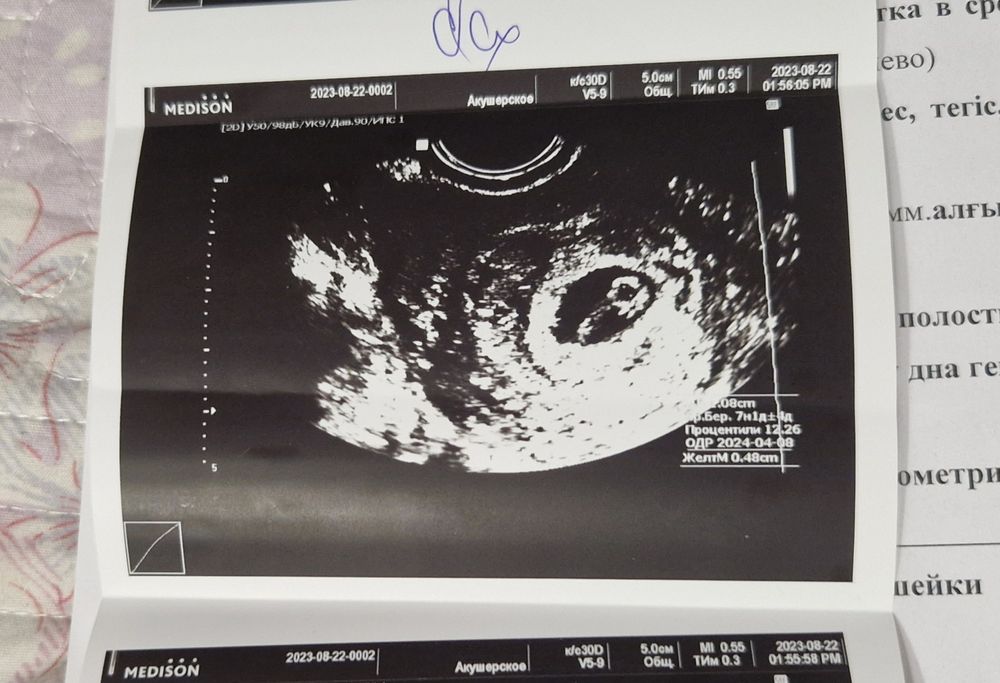

Изображение 7,2

Nazira Khairullina, тут 0,8см

Nazira Khairullina, 1 см

Изображение 7 недель и 1 день